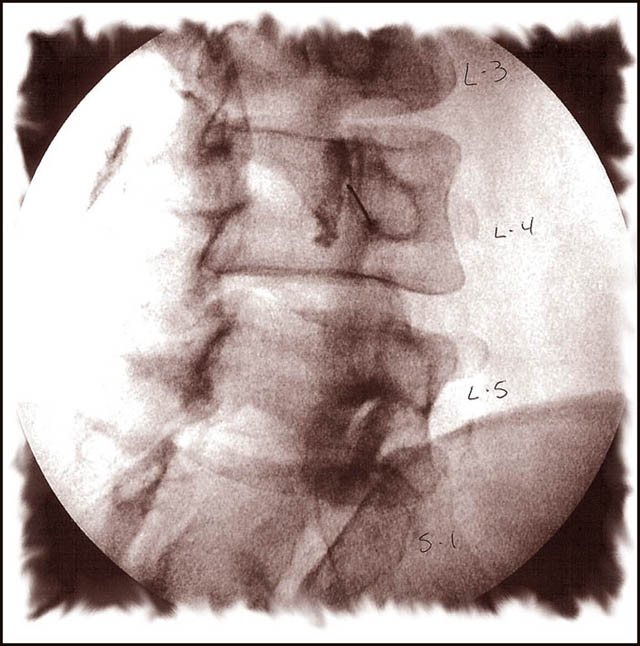

Facet Friday Spine/Vertebra courtesy of ks Fluoroscopic photo courtesy Dr. Robert Brown My day begins lying face down in Surgery Room #2. A slow IV sedation drip running into a vein on the back side of my right hand. The OR nurses were asking me about one of my finger rings. As I attempted to explain it?s relevance and relationship to Devils Tower, seven sisters being chased by a giant bear and the Pleiades star cluster, I quickly wondered off into a very deep chemically induced sleep? With the aid of a fluoroscope Dr. Brown directed the first of five hollow needles through my skin and muscles of my back to the sensory nerves located in the facet joints. The fluoroscope monitor allowed doc Brown to guide the needle (in real-time) to make sure it was on target to hit the specific facet joint. When the needle was in correct position, he injected the anesthetic and corticosteroid meds directly into the facet joint capsule (injection/needle is show in above photo, section L4). The needle was removed and the complete process was then duplicated on the next four joint locations. Overview Lumbar facet joints are small joints located in pairs in your lower back. These joints provide stability and guide motion in your spine. This procedure deadens the nerves carrying pain signals to the brain. A facet injection includes both a long-lasting corticosteroid and an anesthetic numbing agent. The drugs are delivered to the facet joint, either inside the joint capsule or in the tissue surrounding the joint capsule. Each vertebra has four facet joints; one pair that connects to the vertebra above and one pair that connects to the vertebra below.